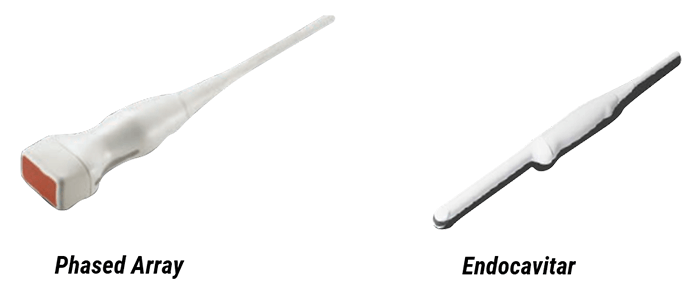

- The Phased array transducer, which is the most commonly used, has a small footprint and low frequency. It is used for Brain, abdominal, and cardiac examinations

- The Endocavitary transducer, that is mainly used for gynecological and prostate examinations